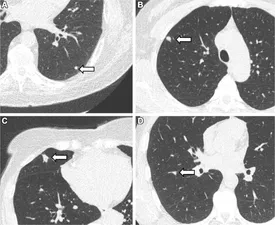

تحقیقات جدید نشان میدهد که داروی متفورمین، که معمولاً برای درمان دیابت نوع ۲ تجویز میشود، ممکن است در مبارزه با سرطان ریه نیز مؤثر باشد. طبق گزارشها، این دارو میتواند به افزایش اثربخشی داروهای ایمونوتراپی، که برای درمان تومورهای ریه استفاده میشوند، کمک کند.